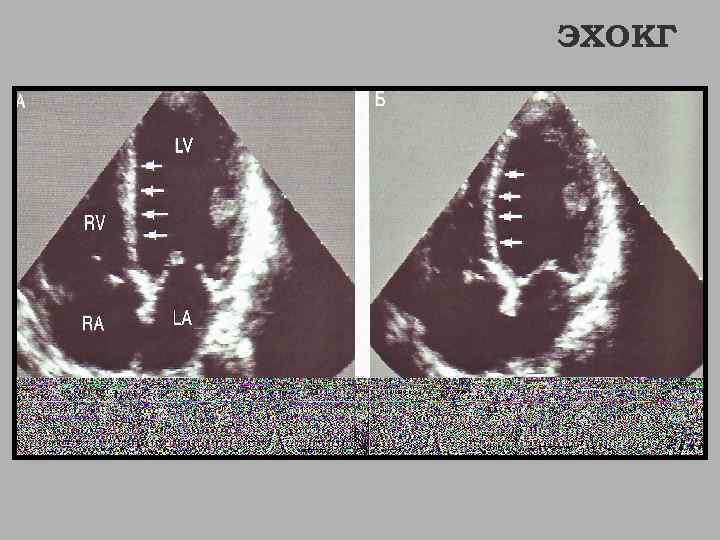

ЭХОКГ

Стрелками обозначены акинетичные сегменты миокарда ЭХОКГ